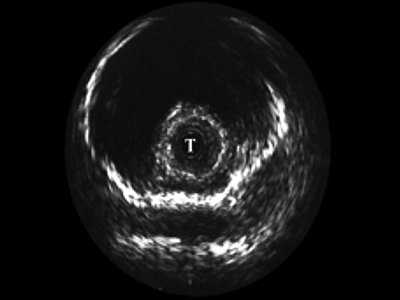

При интрауретральной ультрасонографии в неизмененных отделах мужской уретры по мере проведения датчика мы определяли головку полового члена, губчатое тело, кавернозные тела с окружающими их оболочками, сосуды. В более широком луковичном отделе регистрировались спонгиозная ткань с более тонкой стенкой и прикрепляющимися к ней мышцами (рис. 2).

Рис. 2. Эхограмма нормального луковичного отдела уретры, Т - трансдуктор.